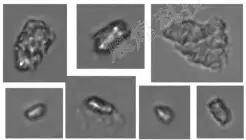

图2:使用YH-FIPS系列流式动态图像法粒度仪对某注射剂进行检测得到的玻璃颗粒的部分图片,玻璃颗粒的典型图像特征是具有一定的透明度与光泽。